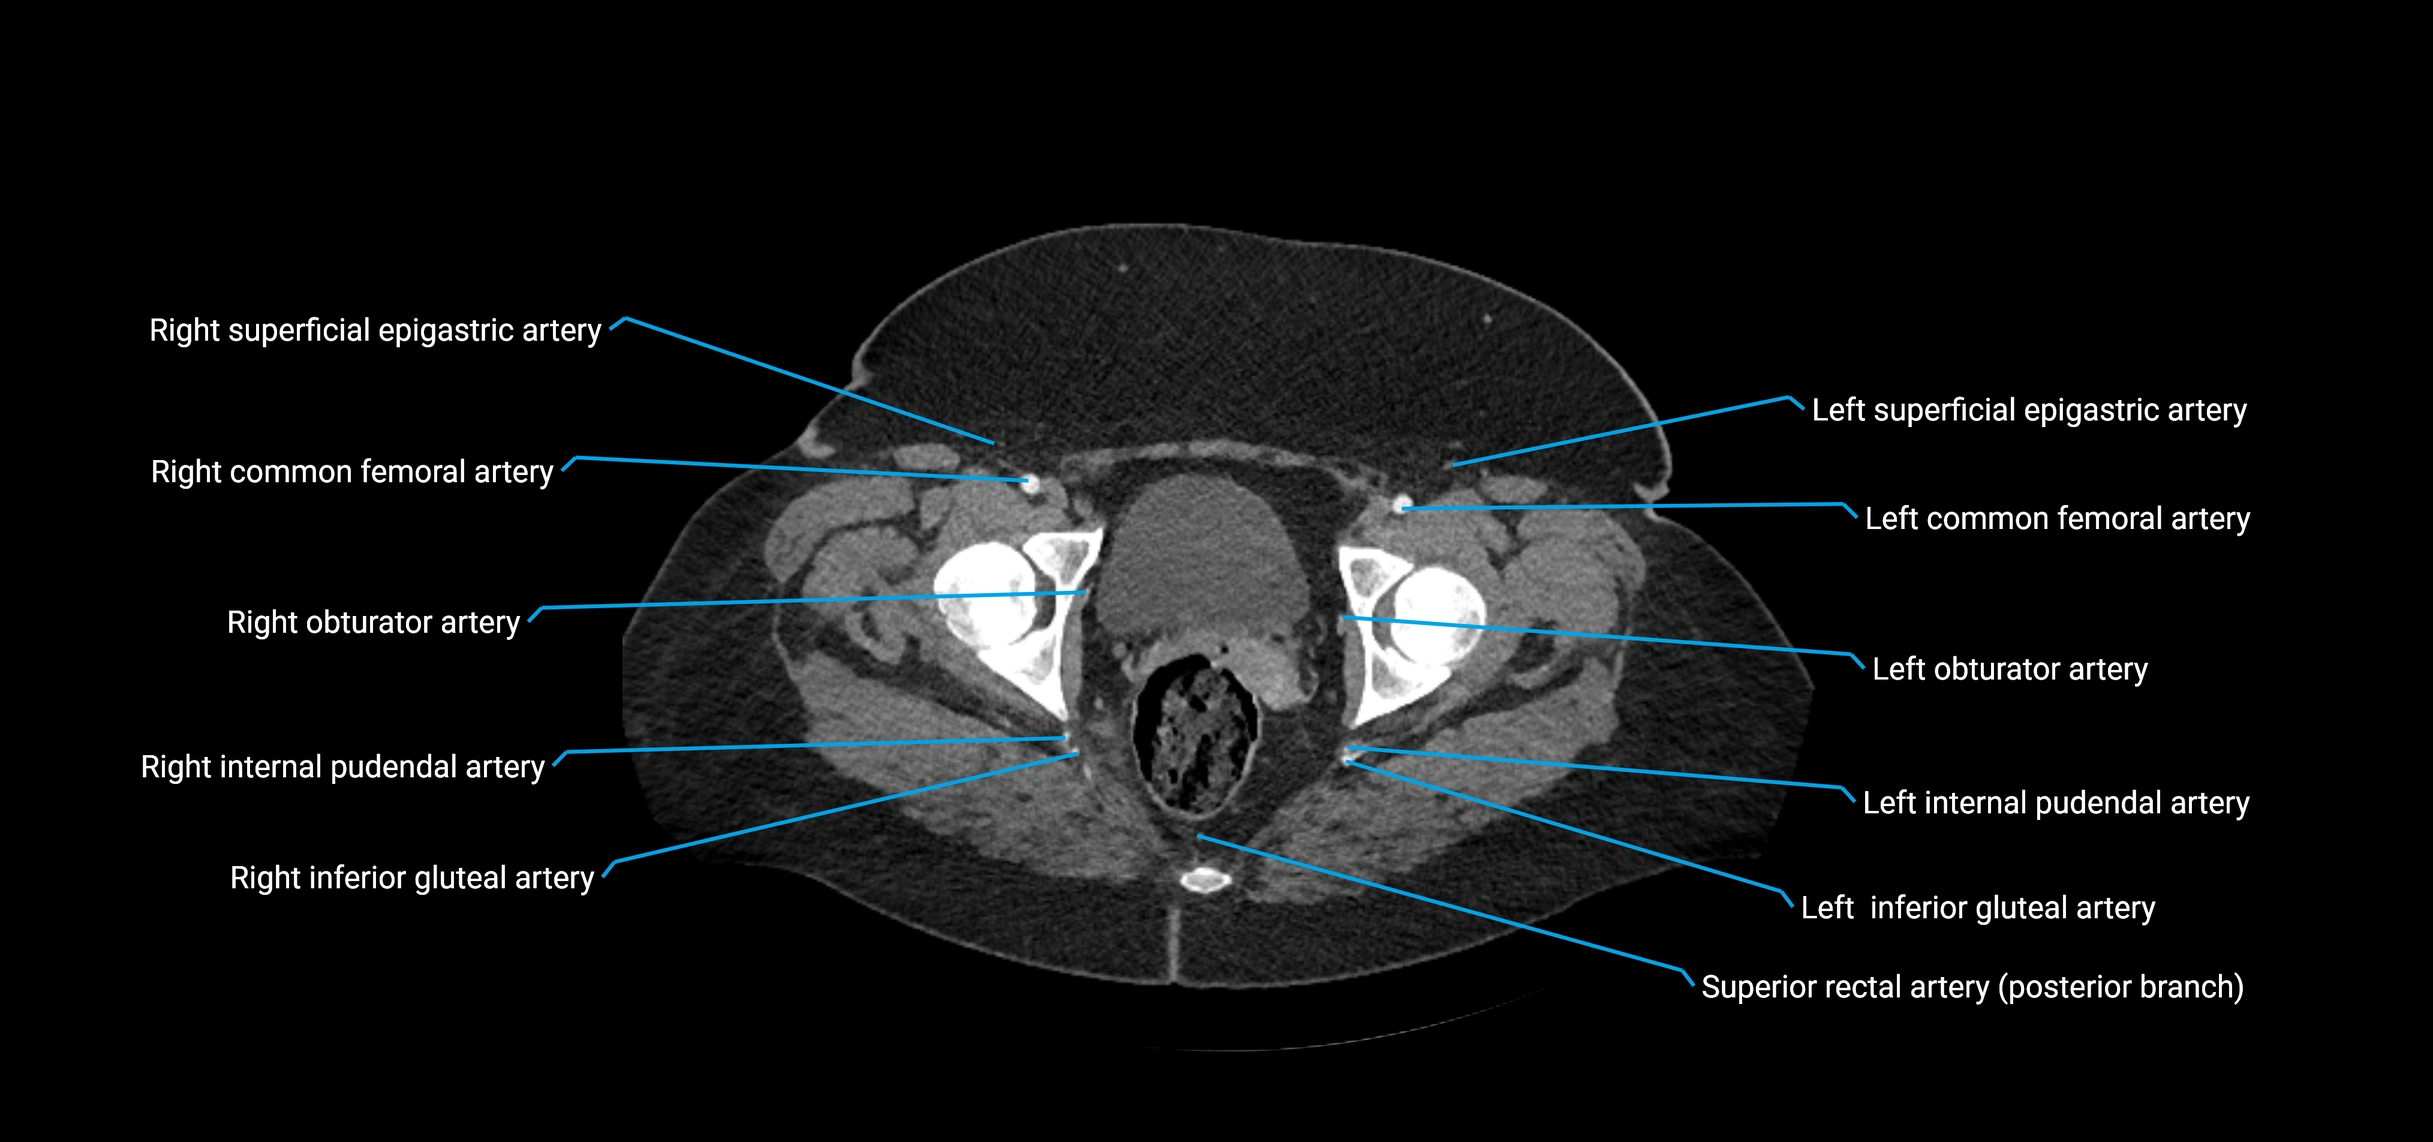

The abdominal aorta is the continuation of the thoracic aorta, beginning at the level of the aortic hiatus of the diaphragm (T12 vertebra) and terminating at the level of the L4 vertebra where it bifurcates into the right and left common iliac arteries. It lies slightly to the left of the midline and courses anterior to the vertebral bodies, surrounded by the retroperitoneal structures of the abdomen.

The abdominal aorta gives off numerous visceral and parietal branches, supplying the abdominal organs, pelvic structures, and lower limbs. It is the main conduit of oxygenated blood from the heart to the abdomen and lower body. The aorta is clinically significant as the common site of aneurysm, dissection, atherosclerosis, and traumatic injury.

Branches

• Unpaired visceral branches: celiac trunk, superior mesenteric artery (SMA), inferior mesenteric artery (IMA)

• Paired visceral branches: middle suprarenal arteries, renal arteries, gonadal arteries (testicular or ovarian)

• Parietal branches: inferior phrenic arteries, lumbar arteries, median sacral artery

• Terminal branches: right and left common iliac arteries

CT images

image